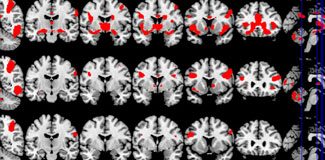

Sonuçlarda porno bağımlılığı ile uyuşturucu bağımlılığı sorunları yaşayan bireylerin beyin aktiviteleri benzer özellikler gösteriyor. Her iki unsurda da beyin aktivitelerinin beynin üç bölgesinde yoğunlaştığı, bunun normal insanlarda bu seviyede görülmediği de açıklandı.